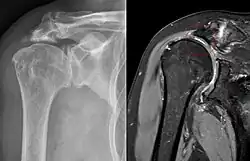

Ursächlich für die nicht artifiziellen Neogelenke kann z. B. eine nicht behandelte Luxation sein, bei der der luxierte Knochen an einer anderen Stelle wieder mit Knochen in Kontakt kommt und durch allmähliche Umformung dieser beiden sich eine gelenkähnliche Form und eventuell auch Funktion ausbildet.[3] Weitere Ursachen können der Verlust von anatomischen Strukturen durch Trauma oder Degeneration sein, die normalerweise zwischen zwei Knochen liegen und so einen Abstand zwischen ihnen halten. Ein häufig vorkommendes Beispiel hierfür ist die Ausbildung eines Neogelenks zwischen Oberarmkopf und Acromion nach Schädigung der Rotatorenmanschette vor allem des Musculus supraspinatus.[4]